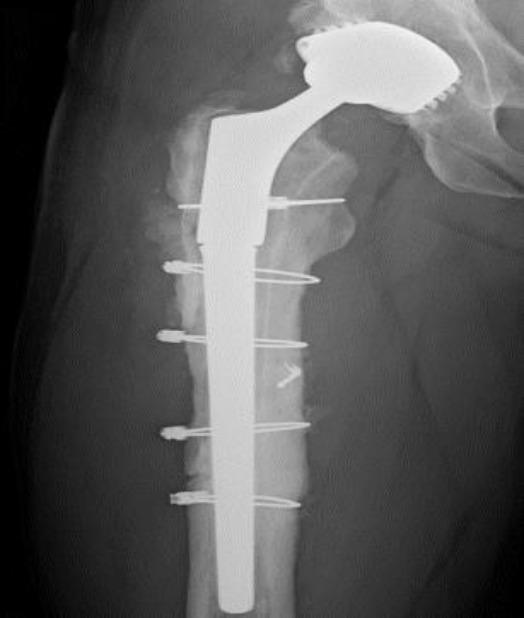

模块化牢固固定型髋关节翻修柄骨折:一例报告及文献综述

Modular Well-Fixed Hip Revision Stem Fracture: A Case Report and Literature Review.

This study presents a case of repeated prosthetic fractures in a modular hip prosthesis in a 56-year-old male patient. After the initial implantation of a modular total hip prosthesis in 2006, the patient experienced two instances of prosthetic implant fractures over seventeen years. In this study, we analyze the clinical case, explore potential underlying causes of this complication, and delve into current indications and strategies for the revision of fractured prosthesis stems. The discussion is informed by a literature review and underscores the significance of selecting appropriate revision techniques to address this challenge.

摘要

本研究报告了一例56岁男性患者模块化髋关节假体反复发生假体骨折的病例。2006年首次植入模块化全髋关节假体后,该患者在十七年中经历了两次假体植入物骨折。在本研究中,我们分析了该临床病例,探讨了这种并发症的潜在根本原因,并深入研究了目前骨折假体柄翻修的适应症和策略。讨论以文献综述为依据,并强调选择合适的翻修技术来应对这一挑战的重要性。